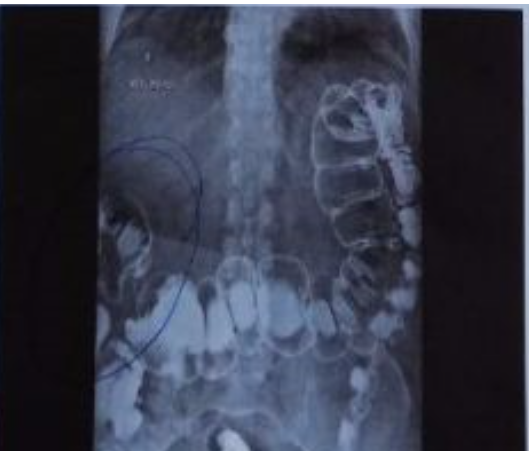

O EXAME DEMONSTRADO É :

1.URETROCISTOGRAFIA RETRÓGRADA ( CONSIDERAR CONTEXTO DO TRAUMA )

2.DEMONSTRA LESÃO DE URETRA .

LEMBRANDO QUE NESSE CASO , NÃO PODEMOS FAZER CATETERIZAÇÃO VESICAL .

* SE A URETROCISTOGRAFIA ESTIVESSE NORMAL DEVERÍAMOS REALIZAR CISTOGRAFIA.